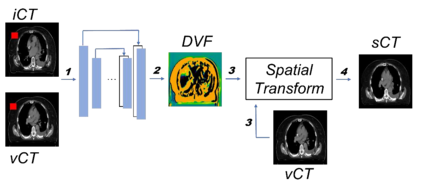

Purpose: In some proton therapy facilities, patient alignment relies on two 2D orthogonal kV images, taken at fixed, oblique angles, as no 3D on-the-bed imaging is available. The visibility of the tumor in kV images is limited since the patient's 3D anatomy is projected onto a 2D plane, especially when the tumor is behind high-density structures such as bones. This can lead to large patient setup errors. A solution is to reconstruct the 3D CT image from the kV images obtained at the treatment isocenter in the treatment position. Methods: An asymmetric autoencoder-like network built with vision-transformer blocks was developed. The data was collected from 1 head and neck patient: 2 orthogonal kV images (1024x1024 voxels), 1 3D CT with padding (512x512x512) acquired from the in-room CT-on-rails before kVs were taken and 2 digitally-reconstructed-radiograph (DRR) images (512x512) based on the CT. We resampled kV images every 8 voxels and DRR and CT every 4 voxels, thus formed a dataset consisting of 262,144 samples, in which the images have a dimension of 128 for each direction. In training, both kV and DRR images were utilized, and the encoder was encouraged to learn the jointed feature map from both kV and DRR images. In testing, only independent kV images were used. The full-size synthetic CT (sCT) was achieved by concatenating the sCTs generated by the model according to their spatial information. The image quality of the synthetic CT (sCT) was evaluated using mean absolute error (MAE) and per-voxel-absolute-CT-number-difference volume histogram (CDVH). Results: The model achieved a speed of 2.1s and a MAE of <40HU. The CDVH showed that <5% of the voxels had a per-voxel-absolute-CT-number-difference larger than 185 HU. Conclusion: A patient-specific vision-transformer-based network was developed and shown to be accurate and efficient to reconstruct 3D CT images from kV images.